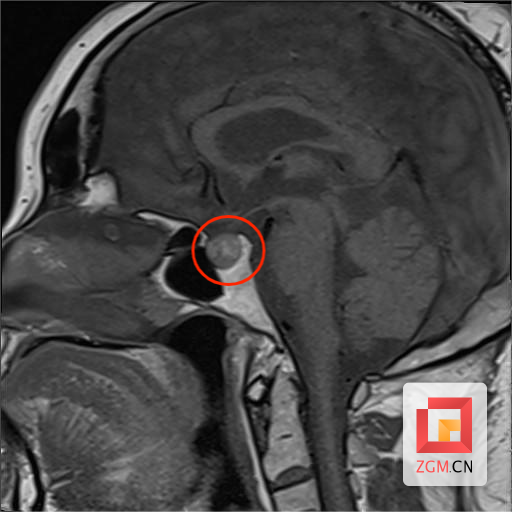

入院后,经完善相关检查,提示钟女士皮质醇升高并节律消失,头颅MRI检查提示垂体右份存在1cm结节,考虑垂体瘤。